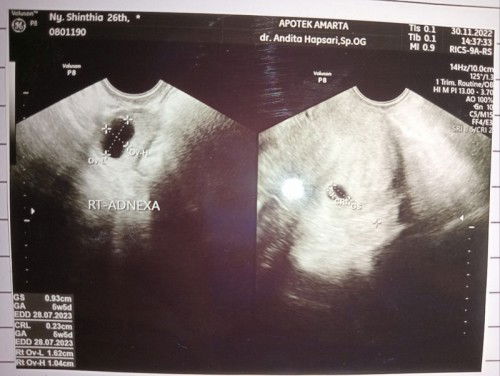

3 hari k belakang saya flek merah muda sedikit udh berenti skrg muncul lg flek darah lumayan banyak langsung usg ternyata ancaman keguguran , uk 5w5d ternyata, perhitungan di aplikasi udh 8minggu . Di kasih microgest 200mg dan vitamin serta bedrest total . Apa ada keluhan bunda2 stelah minum microgest? Sharing dong bun 🥰#firstmom #ingintahu